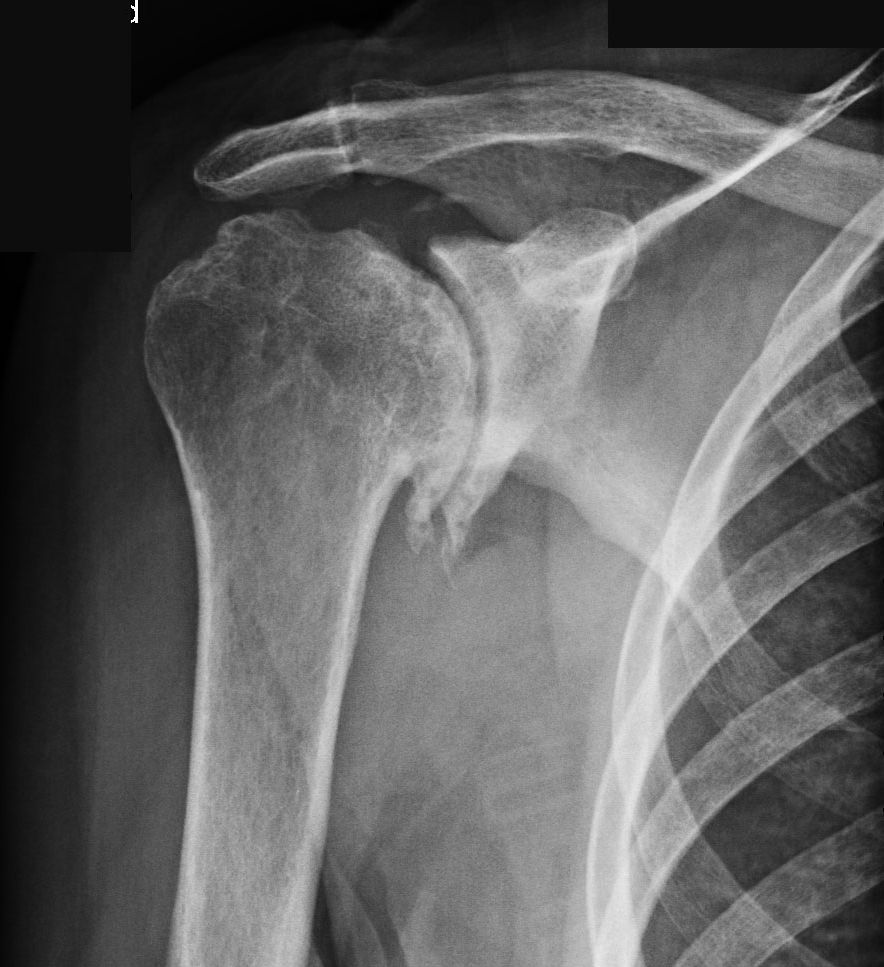

- Рентгенография в двух проекциях. Данный метод отличается доступностью, простотой и низкой стоимостью (в большинстве поликлиник он бесплатный). Деформирующий артроз на рентгеновском снимке проявляется сужением суставной щели, наличием микрокист, остеофитов, признаками склероза подхрящевых структур, подвывихами и зонами окостенения в области суставной щели.